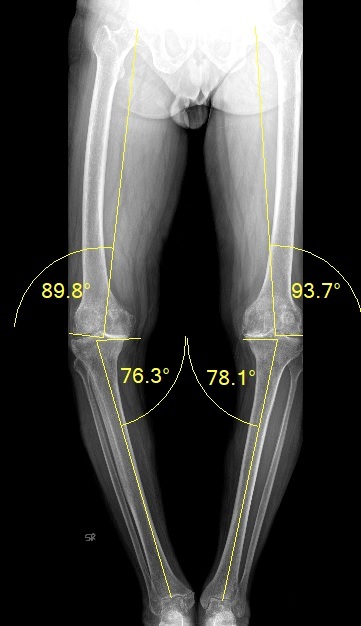

Personalized Knee Replacement In A 82 Years Old Gentleman

Pre Surgical Standing Knee X Ray Both Knee CPAC Type 1